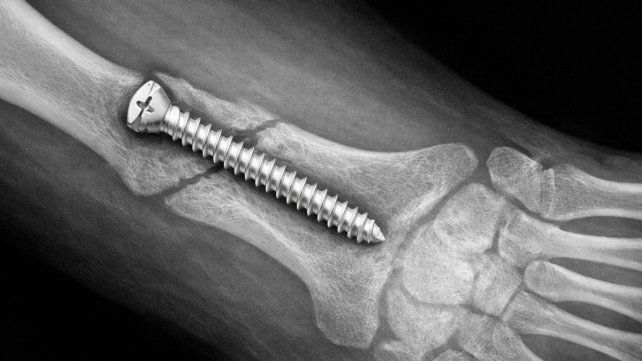

El producto se identifica como STRYKER 10 mm X 28 mm - BIOABSORBABLE - ACL INTERFERENCE SCREW - REF 234-010-067 - LOT 90905.

- El tornillo original es color gris opaco, mientras que el de la unidad falsificada, tal como se observa a través del pouch transparente, es incoloro.